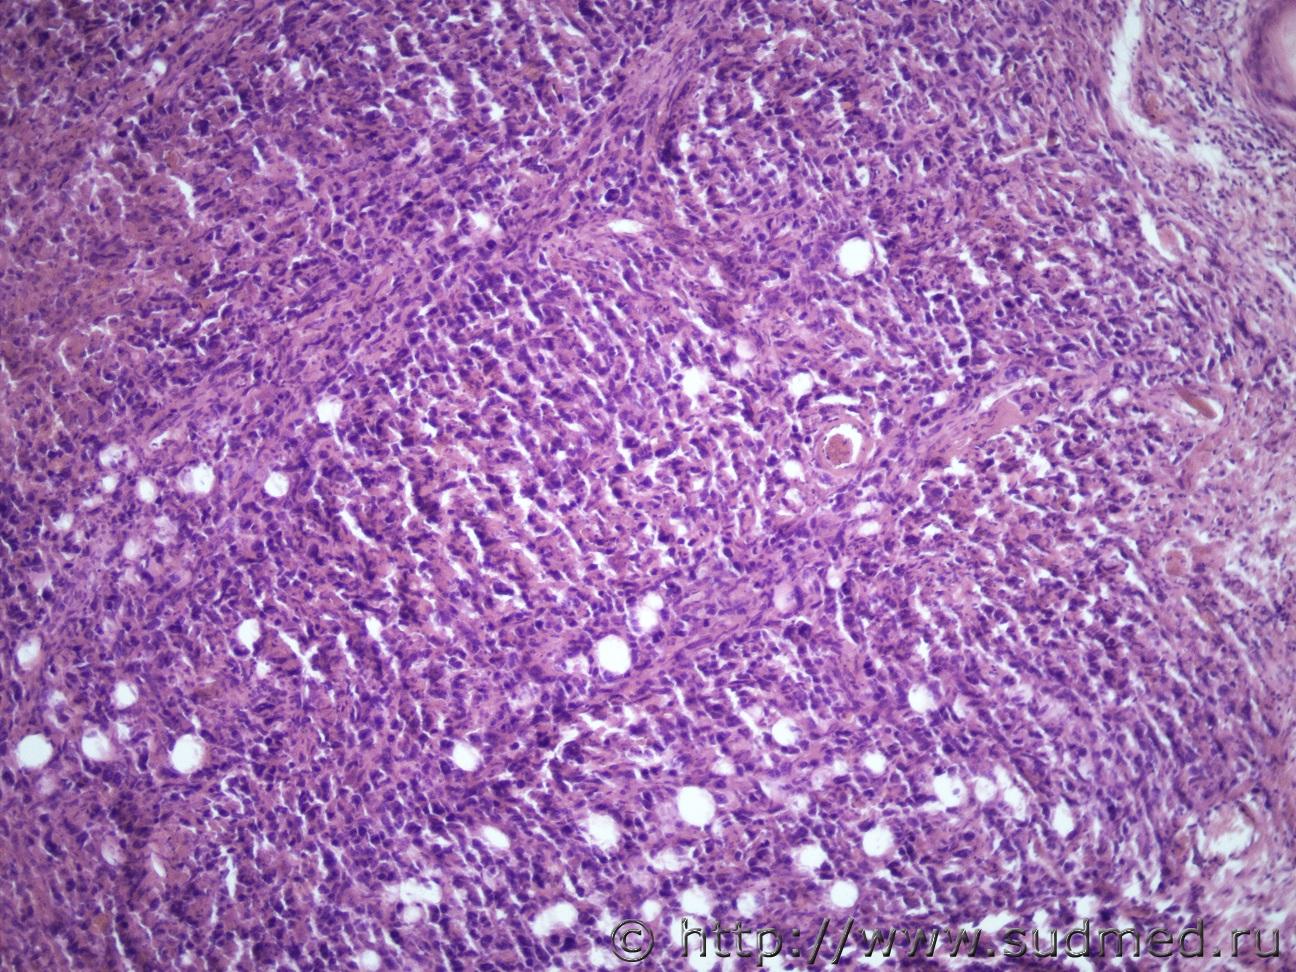

Ув. коллеги доброго дня. Представляю опухоль мочки пр. ушной раковины (9х5х4 см).Судебная медицина - Прикрепленное изображение Судебная медицина - Прикрепленное изображениеСудебная медицина - Прикрепленное изображениеСудебная медицина - Прикрепленное изображениеСудебная медицина - Прикрепленное изображение

Похоже на гигантскую ювенильную ксантогранулему.

Не вижу ксантомных клеток и эозинофилов.

Ювенильная ксантогранулёма встречается главным образом у детей,а в консультируемом случае,скорее всего, умерший недетского возраста.

Тогда соответствует картине Атипической фиброксантоме(AFX)